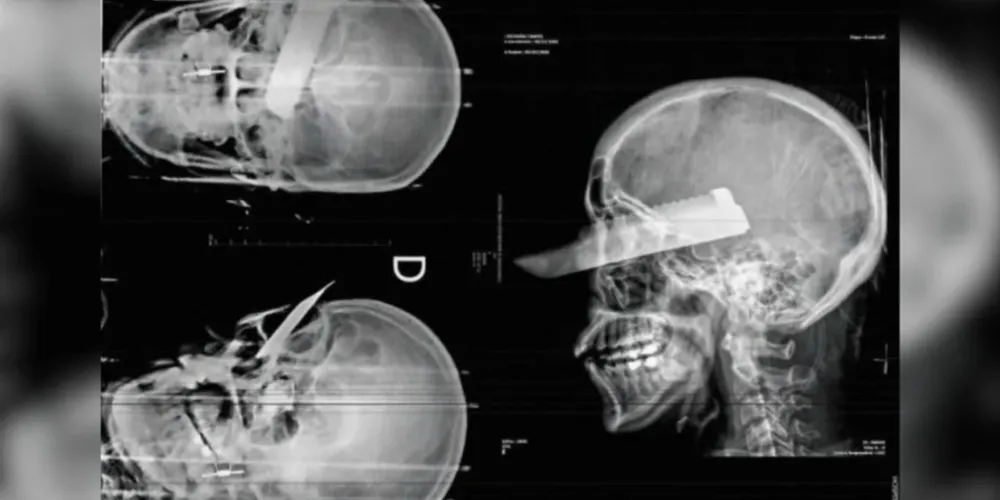

Um homem foi preso, na última segunda-feira (2), suspeito de tentar matar a companheira em São Carlos, no Oeste de Santa Catarina. Ela teve uma faca cravada na cabeça, no olho direito, e ele foi preso em flagrante.

No momento em que ela tentou fugir, foi quando ele a atacou com a facada, que atingiu o rosto e perfurou o olho. A mulher, mesmo ferida, conseguiu escapar e pedir ajuda para um vizinho, enquanto o homem deixou o local.

Tentativa de feminicídio: Um homem foi preso em flagrante suspeito de tentar matar a companheira em São Carlos. A vítima foi atingida com uma facada no rosto, que perfurou o olho direito.